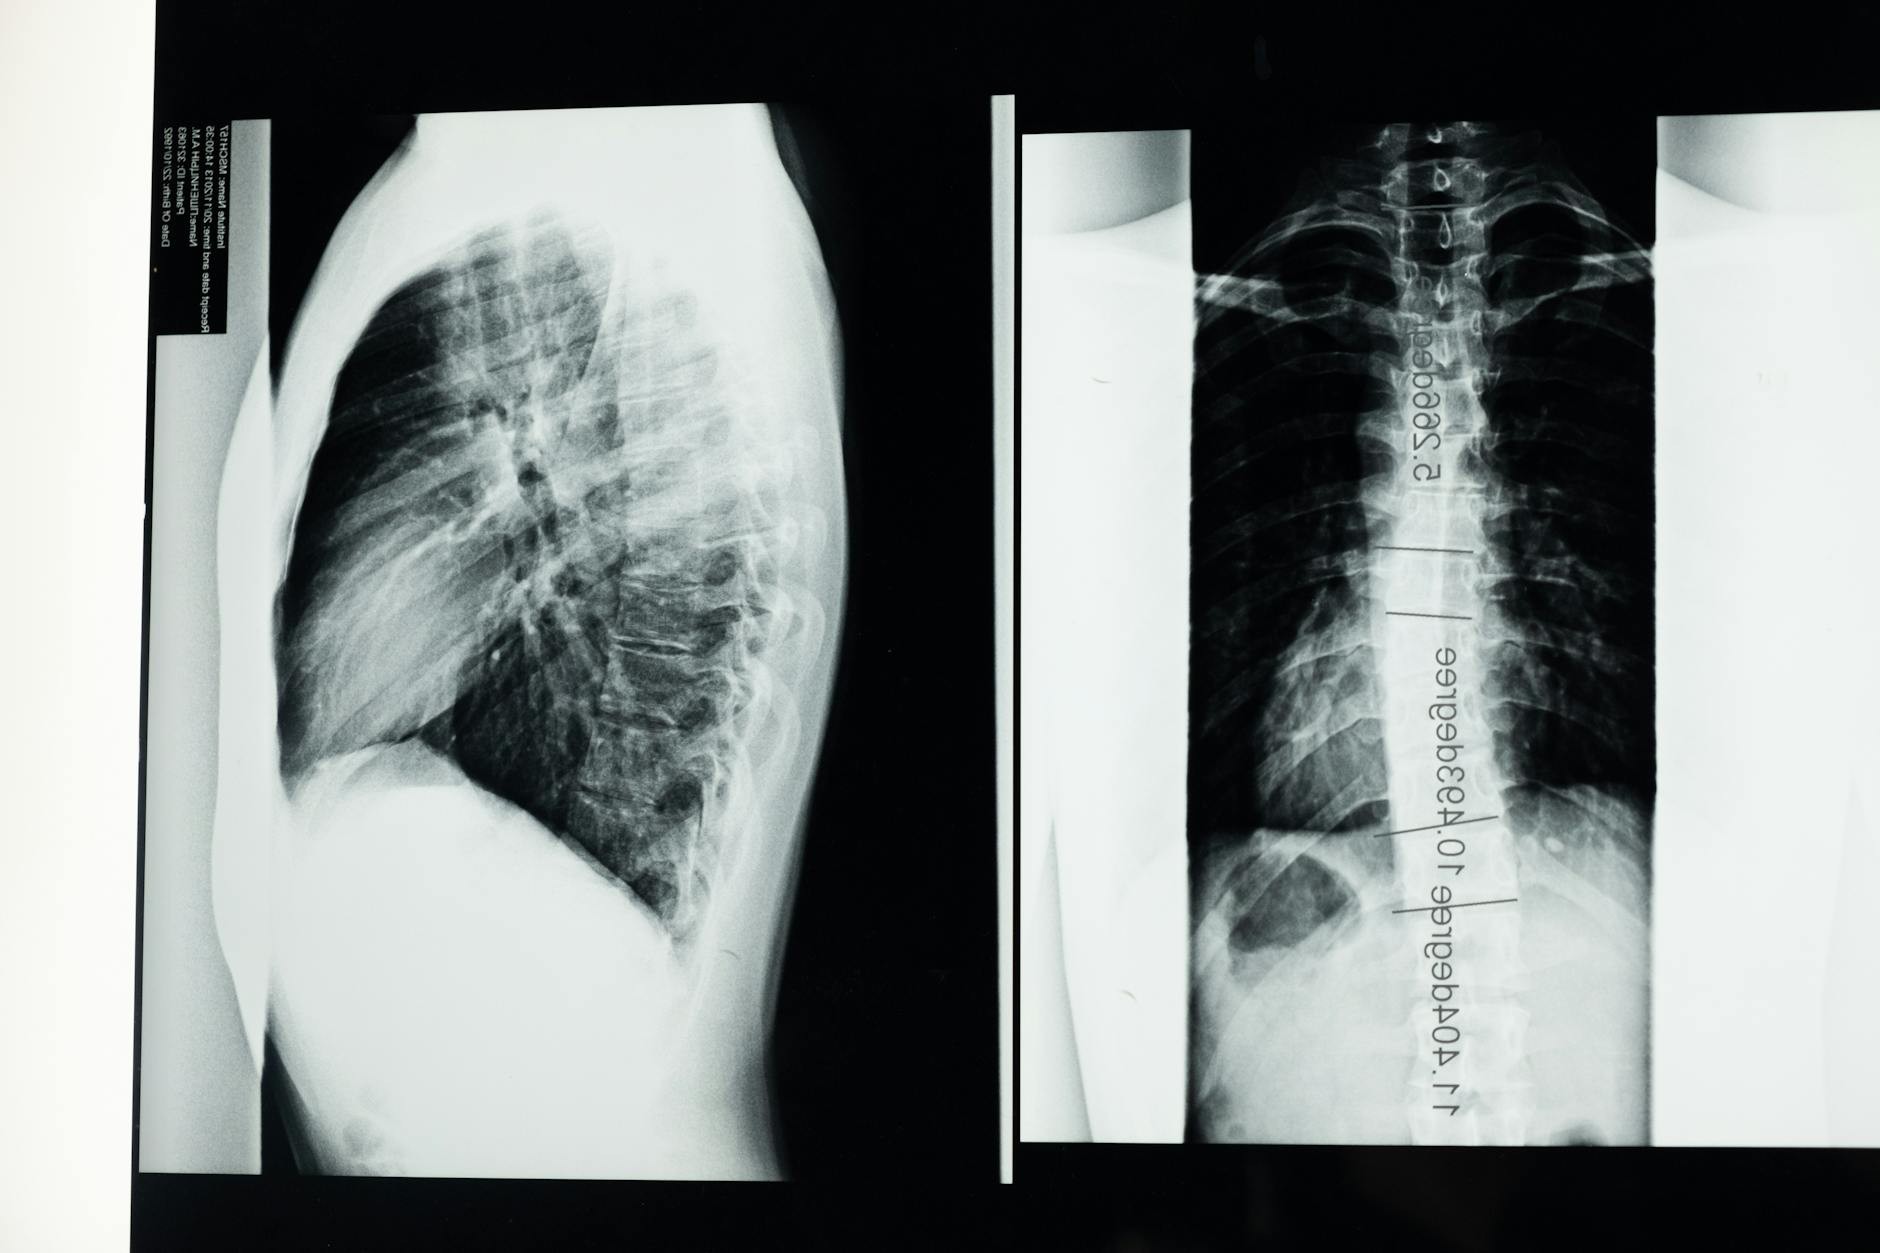

Toksoplazmoza choroba zakaźna. Toksoplazmoza wywołana jest przez pasożyta Toxoplasma gondii. Główną przyczyną zakażenia jest spożycie surowego lub niedogotowanego mięsa. Toksoplazmoza u ludzi dorosłych przebiega bezobjawowo. Toksoplazmoza szczególnie niebezpieczna jest dla kobiet w ciąży. Zarazki bowiem przedostając się do płodu powodują uszkodzenie rozwijających się narządów. Zakażenie w I trymestrze ciąży może doprowadzić do poronienia. Dlatego niezbędna jest diagnostyka kobiet planujących ciążę i ciężarnych.